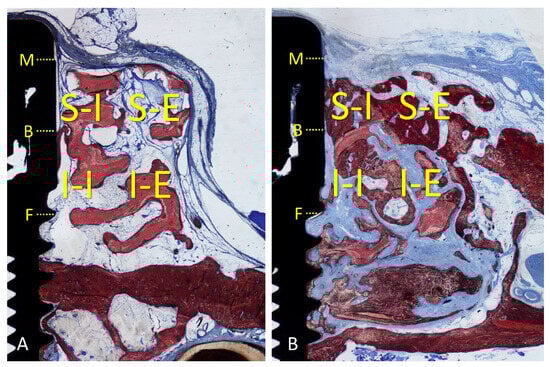

3.2. Descriptive Histological Evaluation